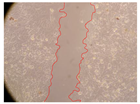

| 2 h | 8 h | 12 h | 24 h | |

| Control | ![]() | ![]() | ![]() | ![]() |

| Samples | 0 h | 2 h | p-Value | 8 h | p-Value | 12 h | p-Value | 24 h | p-Value |

|---|---|---|---|---|---|---|---|---|---|

| Control | 3.8 | 3.79 | - | 3.13 | - | 2.93 | - | 2.65 | - |

| P. viridis 250 mg/L | 2.36 | <0.001 | 2.06 | <0.001 | 1.5 | <0.001 | 0.53 | <0.001 | |

| P. viridis 500 mg/L | 2.97 | <0.001 | 2 | <0.001 | 1.64 | <0.001 | 0.54 | <0.001 | |